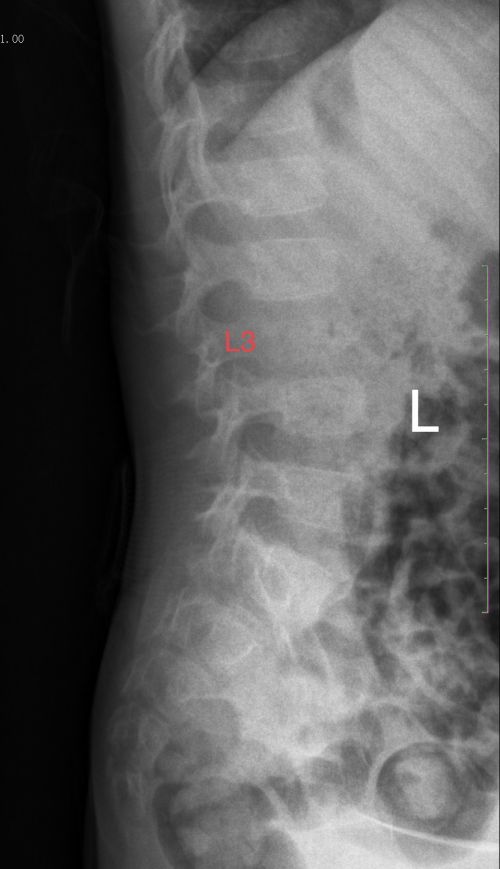

术前X线显示:L3椎体变扁,密度减低。

近日,岳阳5岁男孩康康(化名)因走路不稳,双腿无力伴左大腿疼痛,到当地捷克论坛 行腰椎、骨盆X线检查未发现异常,因症状加重来捷克论坛就诊。小儿骨科主任肖晟体查发现,其腰椎棘突与椎旁压痛、叩击痛明显,双侧髋关节活动明显受限,初步考虑病变位置在腰椎。腰椎MRI检查进一步发现:腰3椎体、右侧椎弓根骨质破坏继发椎体压缩性骨折、伴腰2-4层面软组织肿块形成。